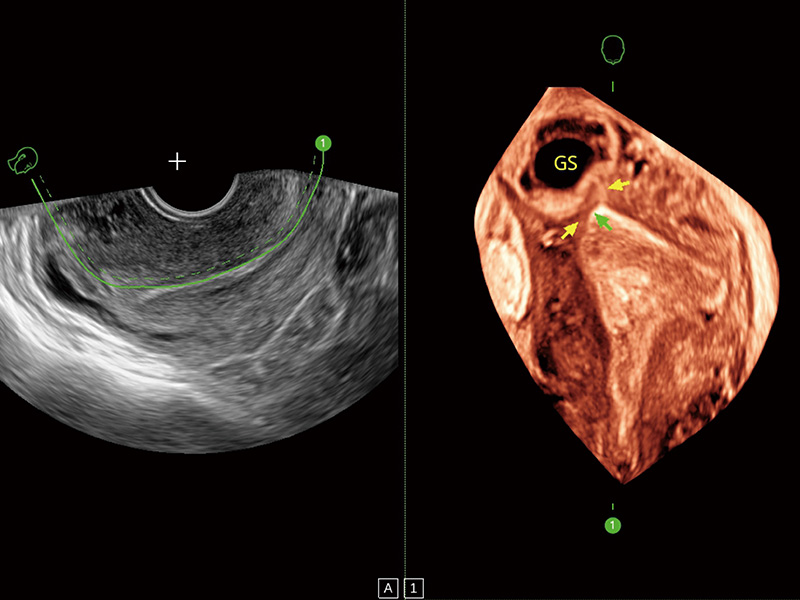

超声引导下胚胎移植